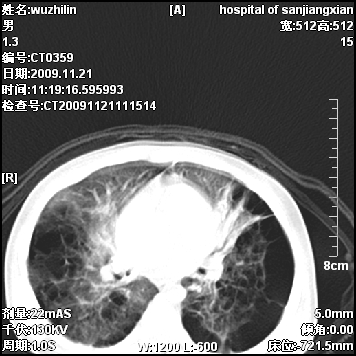

弥漫性薄壁囊腔,胸膜下及肺底部占优势,双上肺磨玻璃密度影,首先考虑特发性肺间质纤维化,其次囊性肺纤维化,肺淋巴管平滑肌瘤病嗜酸性肉芽肿等;要结合临床综合考虑。

两肺布满多个薄壁含气囊腔,以下肺居多,伴磨玻璃样密度影,左侧气胸。两肺发育不全、两肺多发肺囊肿并感染,其次考虑肺囊腺瘤。